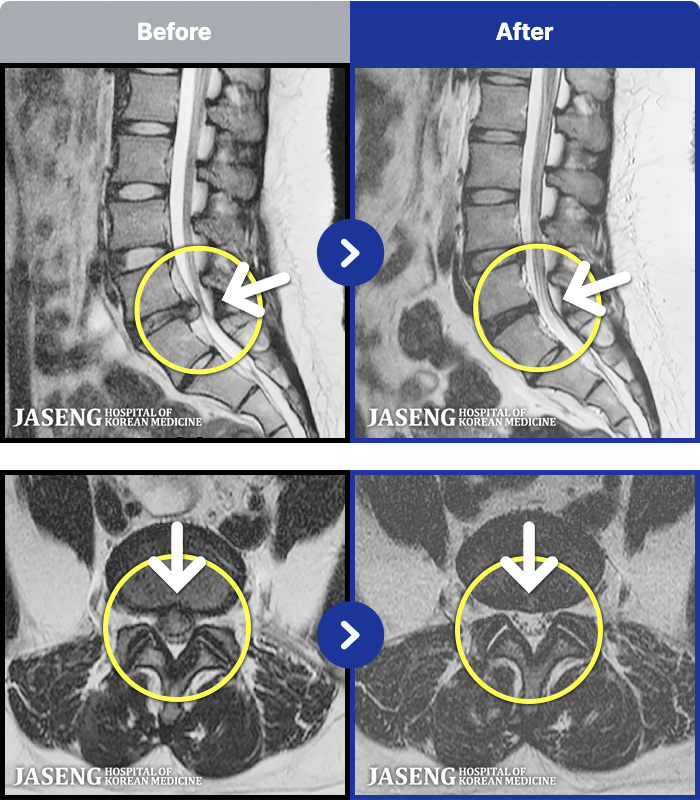

ȯںп Ǹ ǿ ԿǾ, ο ġ ۿ Ƿ ġḦ Ͻñ ٶϴ.